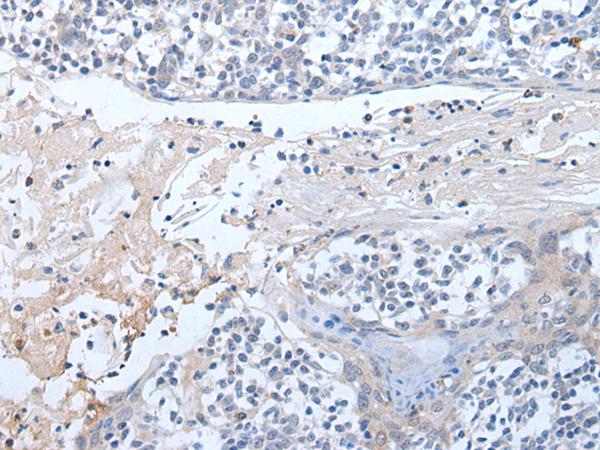

IHC positive control: |

Human colorectal cancer and human tonsil |

IHC Recommend dilution: |

20-100 |